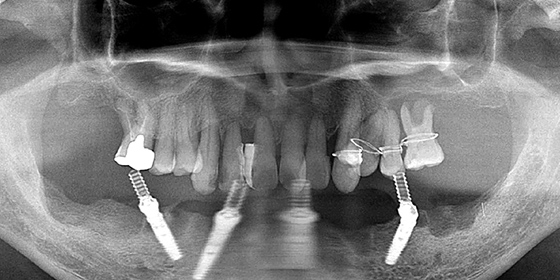

治療前

この症例では下顎の歯周病が特に進行していて、歯がクラグラで噛みにくい為、下の歯を抜歯してオールオン4で治療、上は特に歯周病が進行している左側の大臼歯を抜歯して経過観察することにしました。

治療内容

下の歯の抜歯後インプラント

上の歯の抜歯

手術当日に仮歯装着